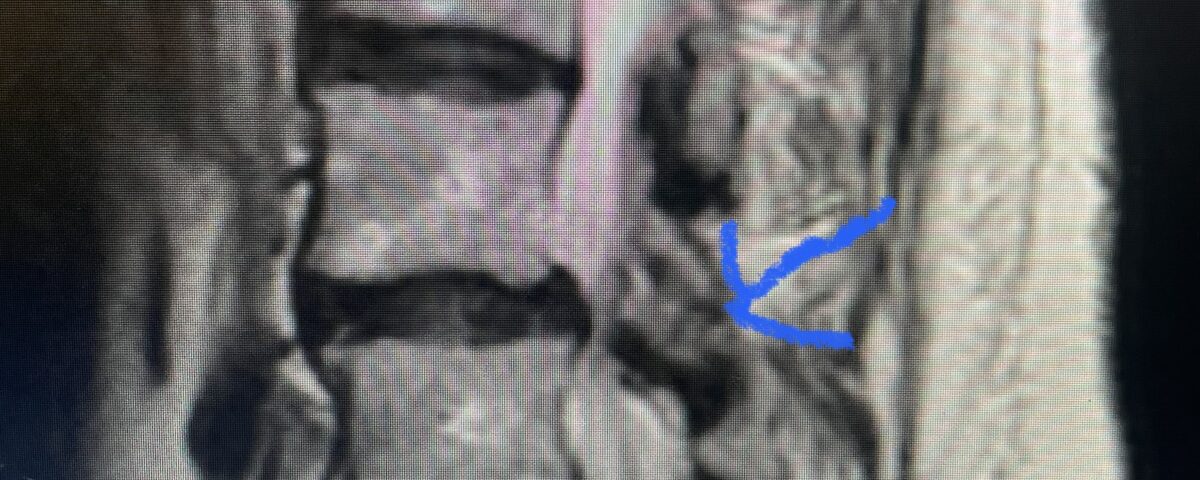

Another patient is a 62 year-old female with progressive low back pain and right leg pain and numbness that radiates to the top of her foot. She tried physical therapy and epidural injections. MRI demonstrated severe L3-4 stenosis and a grade 1 spondylolisthesis (Fig 4). There was L5-S1 and L4-5 disc collapse with modic end-plate changes. Biomechanically because of the significant degeneration of these disc spaces which stiffened the L4-S1 segment more stress was placed on the L3-4 segment, resulting in significant premature degeneration and compensatory stenosis and segmental instability. The MRI also showed pathologically, because of the slip, the L3 inferior processes were more anteriorly oriented and hence contributing to the majority of the lumbar canal compromise. Note the more sagittally-oriented facets in this case compared to the prior case (Fig 5). The patient underwent a decompressive laminectomy with attention of removing the inferior processes of L3 to fully decompress the canal. We also performed an L3-4 fusion with instrumentation (Fig 6). The patient had an uneventful postoperative course with improvement of leg pain. Of note with relief of the disabling leg pain patients are generally very happy. Patients can often manage their low back pain; it is the leg pain that they just can’t tolerate.

Fig 4: Sagittal T2-weighted lumbar MRI demonstrating L3-4 grade 1 spondylolisthesis with severe stenosis (blue arrow)